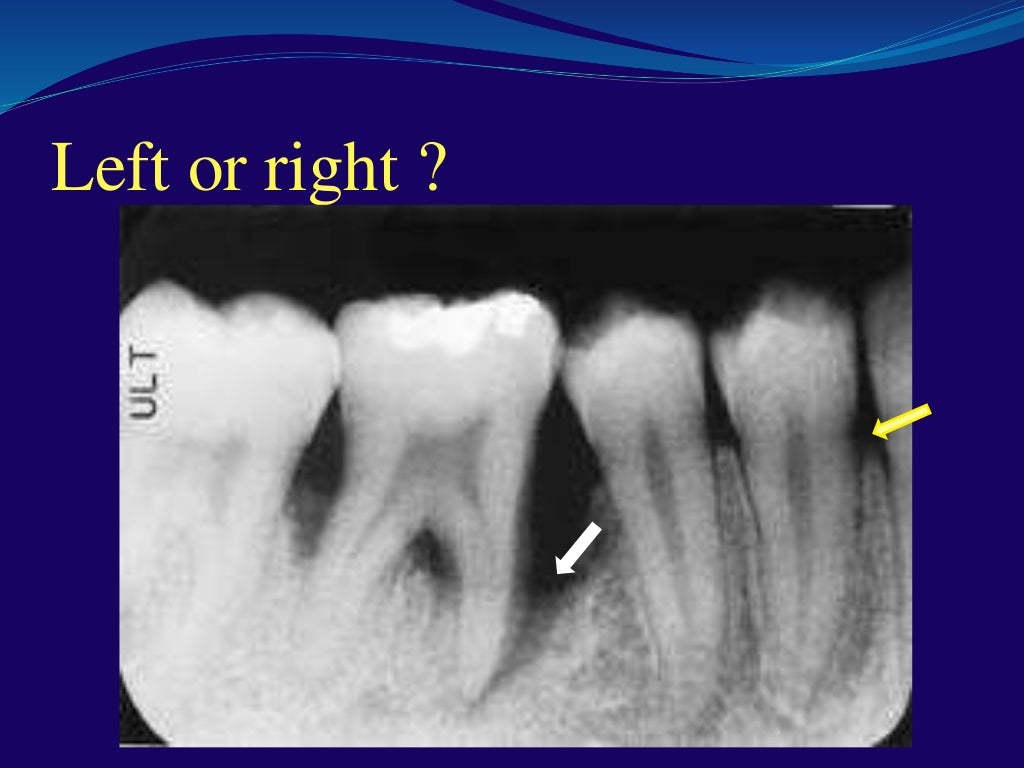

Dental radiology interactive class Artifacts In Dental Radiography Dental screening and interventions are necessary to manage the risk of osteonecrosis [8]. Dental radiography is an indispensable diagnostic tool in modern dentistry,. The effect of metal artifacts on vrf detection was not significantly different between the two. Create artifacts, requiring careful patient assessment before. Dental radiography is an indispensable diagnostic tool in modern dentistry, providing invaluable insights into the. Artifacts In Dental Radiography.